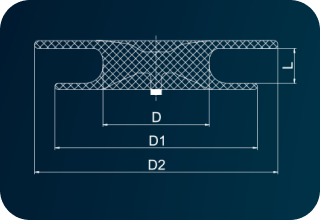

| Code | [D]Waist Diameter (mm) |

[D1]Right Disc Diameter(mm) |

[D2]Left Disc Diameter(mm) |

[L]Waist Length (mm) |

Minimum Recommended Sheath SizeSteerEase™(Fr.) |